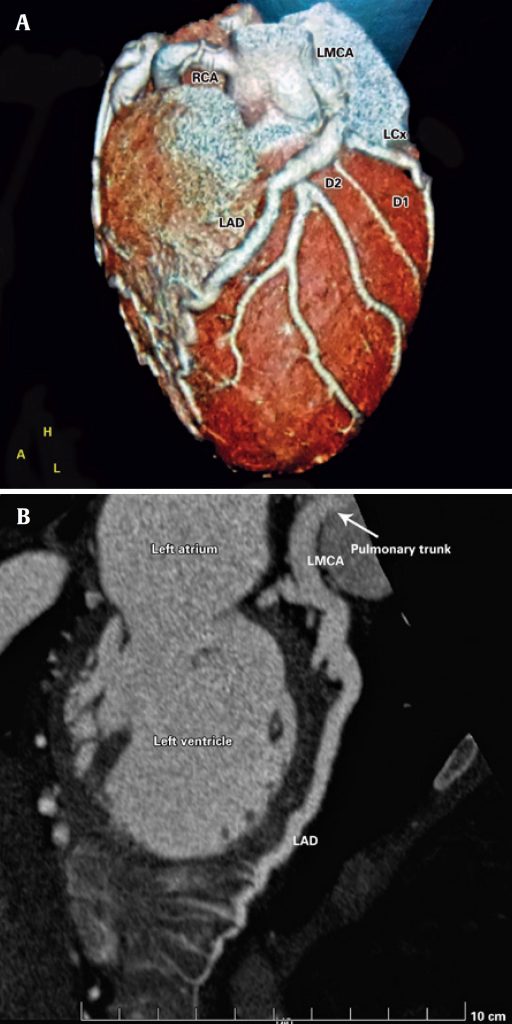

Figure 2

(A and B) Coronary CT angiography. The left main coronary artery (LMCA) originated from the pulmonary artery and measured 7.3 mm in diameter. The left anterior descending artery (LAD) surrounded the apex of the left ventricle and measured up to 6.8 mm in diameter. The left circumflex artery (LCx), which is of great importance, exhibited ectasia in its proximal third and measured up to 6 mm in diameter. The right coronary artery (RCA) originated from the right coronary sinus and measured up to 8 mm at its largest diameter.